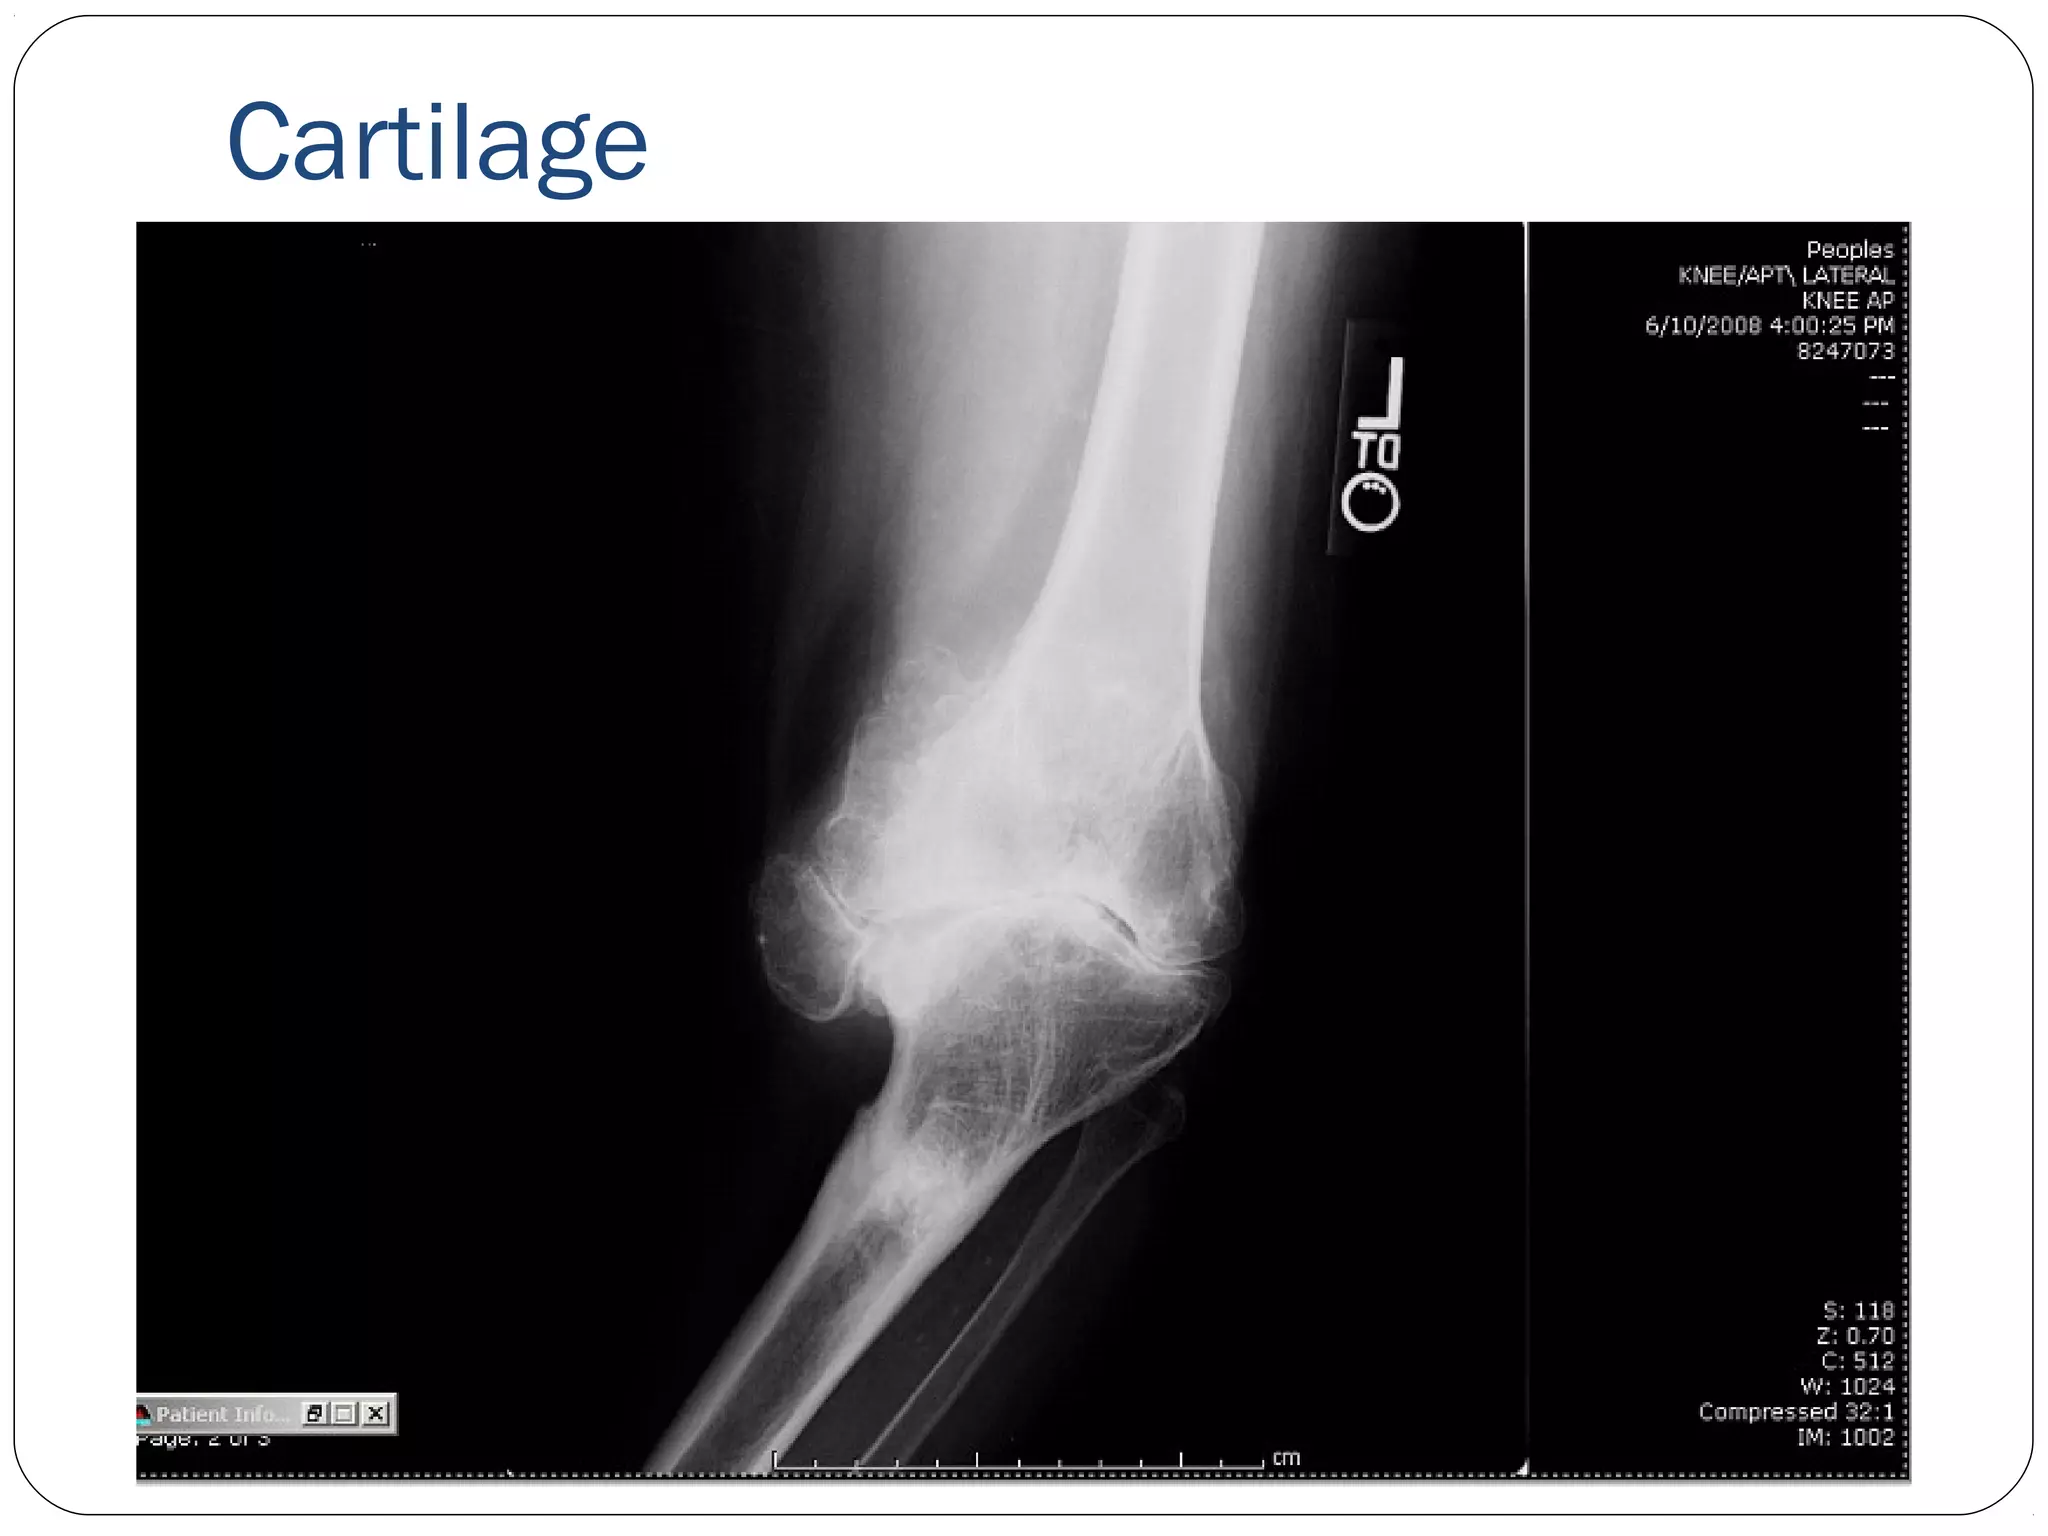

Cartilage

• #30 Who think this is an elbow? Who thinks this is a knee? Image taken in standing